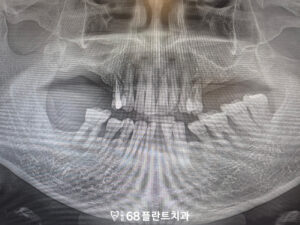

이후 특별한 문제 없이

치유 과정을 안정적으로 거쳤으며,

잇몸과 임플란트의 상태를 확인한 뒤

보철 작업을 진행하였습니다.

보철물 장착 후에는

교합과 기능을 점검하여

일상적인 식사와 저작이

무리 없이 이루어질 수 있도록

마무리하였습니다.

◆ 전 > 후 ◆

치료 마무리 후 사진입니다.

환자분께서는 치아 상실로 인해

식사가 불편하고 어려웠으나,

치료가 마무리된 현재는 임플란트가

안정적으로 자리 잡아

고기와 같은 음식도 무리 없이 씹을 수 있게 되었으며,

전반적인 저작 기능 회복에 대해

만족감을 표현해 주셨습니다.